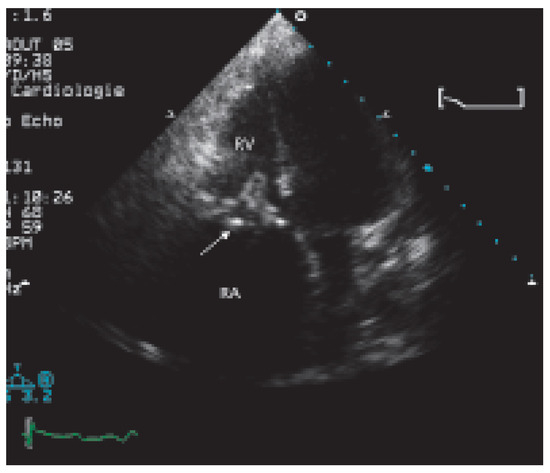

Valve Prosthesis in the Tricuspid Position: An Useasy Relationship

Case report